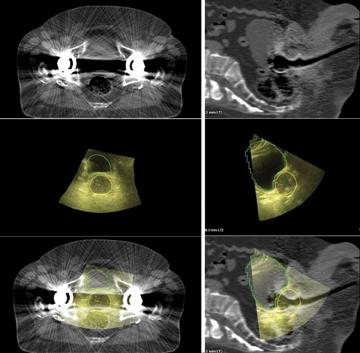

Researchers found older women with invasive breast cancer treated with brachytherapy were at higher risk for a later mastectomy compared to women treated with standard radiation therapy. The University of Texas MD Anderson Cancer Center led the research and published findings in the International Journal of Radiation Oncology.

Cianna Medical Inc., a women’s health company, conducted a large, retrospective study evaluating the safety and efficacy of the Savi breast brachytherapy applicator. Researchers reported favorably low recurrence rates, high rates of survival and excellent cosmetic outcomes. Savi is a strut-based applicator that delivers a form of accelerated partial breast irradiation (APBI), a five-day course of targeted radiation for early-stage breast cancer.